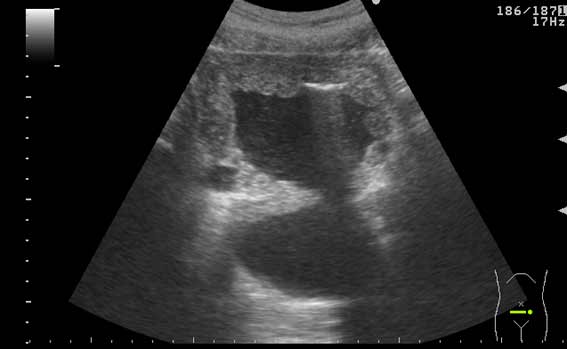

УЗИ мочевого пузыря у пожилого мужчины выявлены следующие изменения.

Signs of chronic urinary retention; evident thickening of the urinary bladder mucosa; large diverticulas. Residual volume evlaluation required; full prostatic assessment is recommended.

But really there are two ones on these pictures.Dr.Mario писал(а):I agree with previous post (Dr. Uzgraph); but there may be much more of them.

неравномерное утолщение стенок мочевого пузыря,признаки застоя в мочевом пузыре,расширенные дистальные отделы мочеточников,на первом снимке-дивертикул?слева,уввеличенная отечная простата

Все верно, за исключением того что простаты на картинках нет. Здорово, что Вы заметили расширение мочеточников. Есть также воздух в МП после цистоскопии.besliu писал(а):неравномерное утолщение стенок мочевого пузыря,признаки застоя в мочевом пузыре,расширенные дистальные отделы мочеточников,на первом снимке-дивертикул?слева,уввеличенная отечная простата